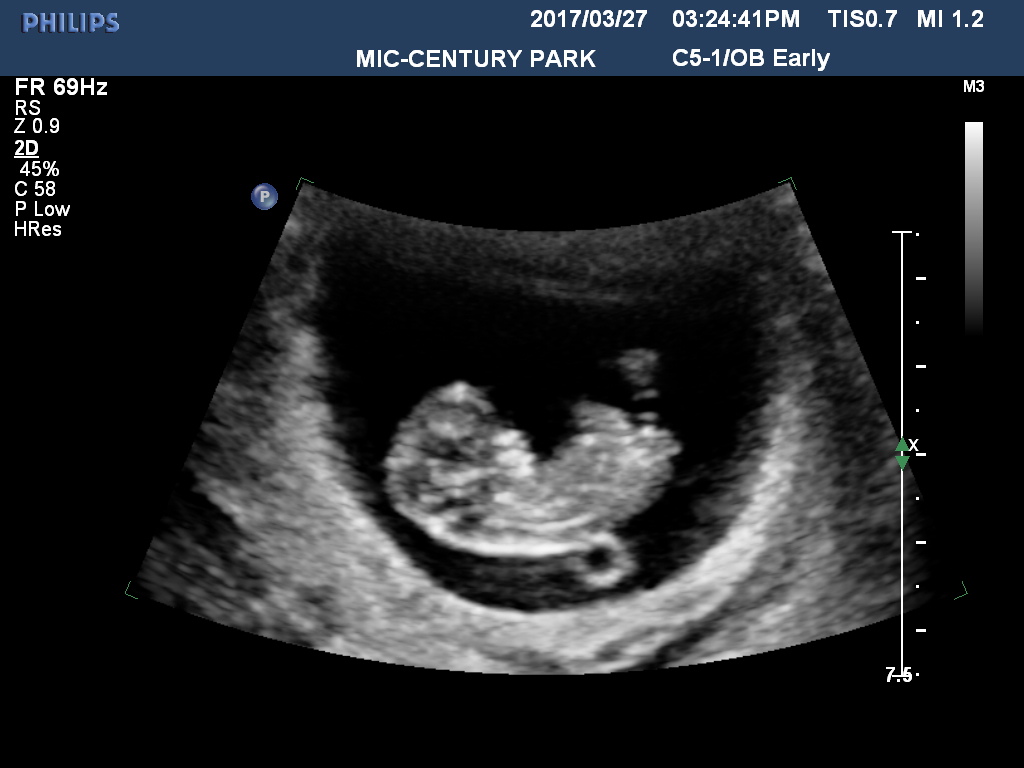

Is 7 Weeks Too Early For A Dating Scan : Dating scan for pregnancy | First Trimester / Dating ... : 7 weeks is definitely not too early to see your baby, but the image might be different from what you imagined.. Early pregnancy symptoms (at 7 weeks). If your periods were irregular, even though it is seven weeks from your last menstrual period, you may still be only five weeks along at a second ultrasound. It's very hard for them to measure when it's that small. No fetal heartbeat after seven weeks gestation It's used to see how far along in your pregnancy you are and check your baby's development.

7 weeks is definitely not too early to see your baby, but the image might be different from what you imagined. Our early scans explained window to the womb from windowtothewomb.co.uk the dating scan will also show if you're expecting twins, triplets, or more (mongelli 2016, nhs 2015a). I never made it to this stage with my last pregnancy as i started spotting 5 days before and was sent for an earlier scan which showed that i had suffered a missed miscarriage. I would wait till 8 weeks but the other halfs away and won't be back till 9 weeks so then may aswel wait for the dating scan. If your periods were irregular, even though it is seven weeks from your last menstrual period, you may still be only five weeks along at a second ultrasound. Is 7 weeks too early for a dating scan??: Early pregnancy symptoms (at 7 weeks). For many women, this means you're 4 weeks at about the time of your missed period, and 6 weeks pregnant about two weeks after your missed period. The size of the baby correlates less and less with its age as time goes on. I will be super worried for the whole trip till. An ultrasound is performed at this stage of pregnancy to confirm your due date, confirm if you are having singles, twins or more and to visualise your baby's heart beating. A dating scan might be recommended before 12 weeks to confirm your due date if you are unsure of your last menstrual period or your date of conception. Your pregnancy is dated from the first day of your last menstrual cycle.

Early pregnancy viability scan (or dating scan) at the birth company in harley street, london. Is 7 weeks too early for a dating scan??: Is 7 weeks too early to do dating ultrasound?: I had 2 mmc's (missed miscarriages) last year and have been bleeding with this pregnancy so have had 2 early scans at the early pregnancy unit so far (7&8 weeks) and have one tomorrow too when i'll be 10 weeks. Transabdominal ultrasound (tau) and also the transvaginal ultrasound (tvu) are valuable diagnostic tools in obstetrics and gynecology. Also known as first trimester screening, early anatomy scan, early pregnancy scan or nuchal translucency scan. I would wait till 8 weeks but the other halfs away and won't be back till 9 weeks so then may aswel wait for the dating scan. We'll go into detail later about what you can expect to see. You may be referred for an early scan because of vaginal bleeding or spotting, or possibly because you have had problems in a previous pregnancy. Before 7 weeks, babies are often so small that the abdominal ultrasound may have trouble picking up the information the doctor wants. Outcome of the baby is because of pregnancy can a blood. Your midwife or doctor will book you a dating. At our clinics we scan from 7 weeks but at this time due dates are not totally accurate as it is very early stages.

At our clinics we scan from 7 weeks but at this time due dates are not totally accurate as it is very early stages. The 12 week scan then pretty much backed the original dates as did the 20 week. It's used to see how far along in your pregnancy you are and check your baby's development. The most common reasons for this private ultrasound scan is to confirm the pregnancy, to check viability and that everything is ok in general. The size of the baby correlates less and less with its age as time goes on.